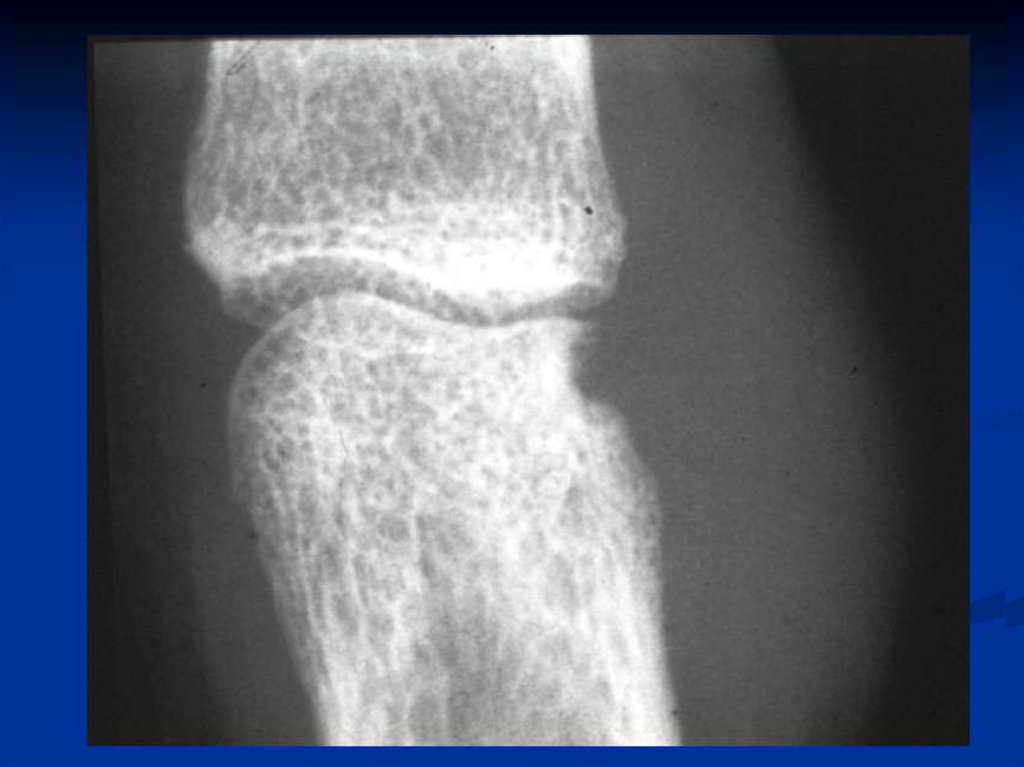

Характеризуется симметричным хроническим эрозивным

артритом (синовитом) периферических суставов и

Необратимые структурные –

эрозии, анкилоз